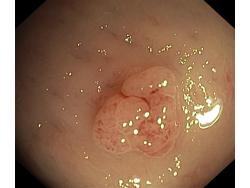

Polipy